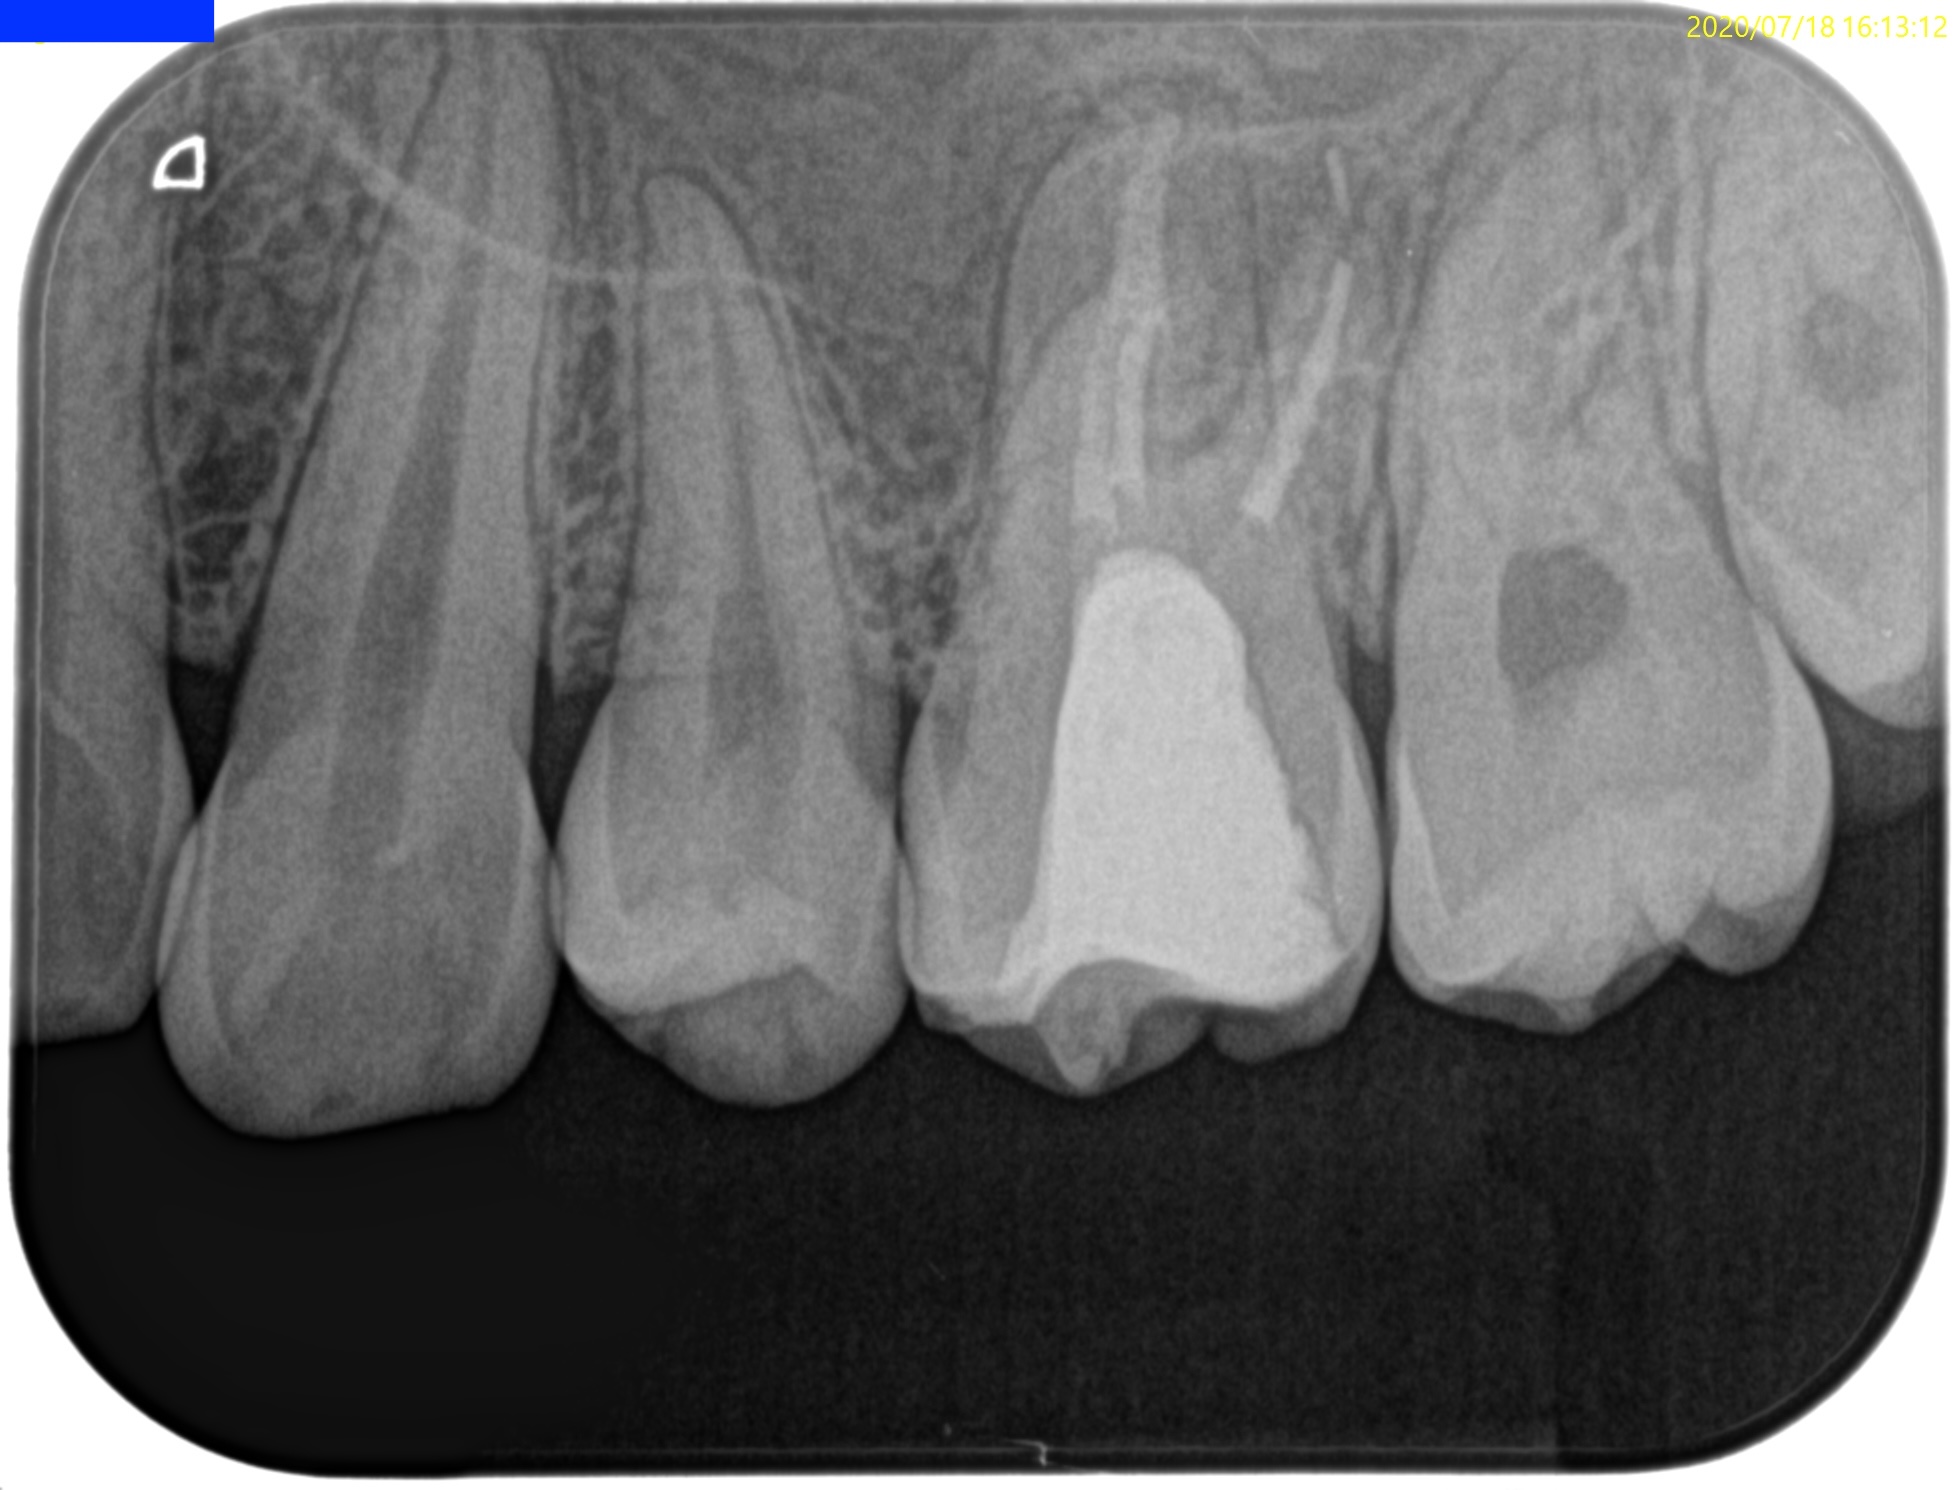

#14 Re-RCT(2020.7.18)